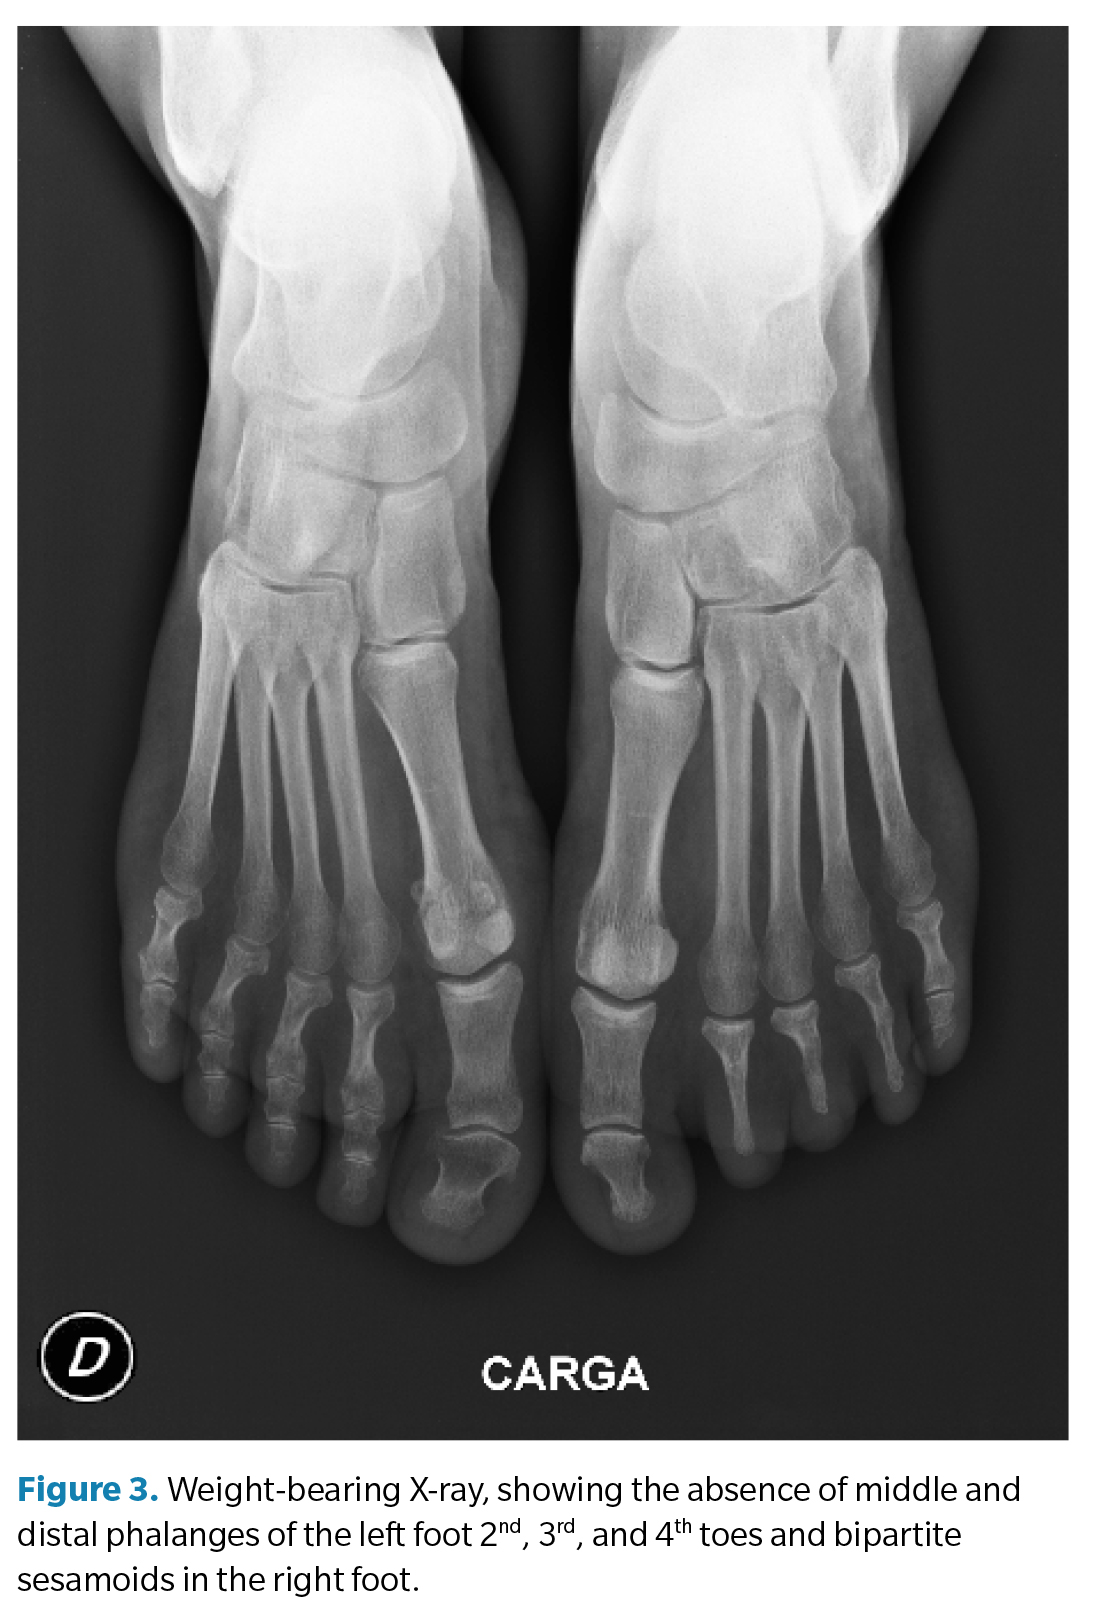

Subsequently, a weight-bearing X-ray was performed in the anteroposterior projection to complement the examination. Exceptionally, the absence of middle and distal phalanges of the 2nd, 3rd, and 4th toes of the left foot was found (Figures 2 and 3). A difference in the metatarsal formula was observed between both feet, showing a minus index in the left foot and a plus-minus index in the right one. Findings were consistent with isolated BBD.

Figure 1. Patient standing, showing the absence of middle and distal phalanges of the left foot 2nd, 3rd, and 4th toes and micronychia affecting the 2nd, 3rd, and 4th toes, along with subungual hematoma on both big toes.